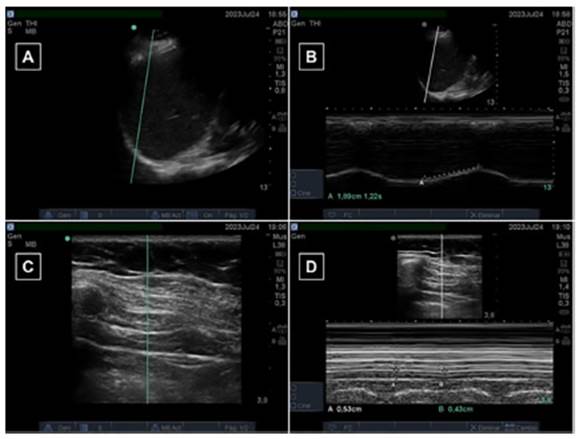

• Diaphragmatic function: a

portable ultrasound machine was used for academic purposes during the study (Fujifilm©

SonoSite M-Turbo), provided by Tecnoimagen S.A. Figure 2 shows various

ultrasound images obtained in both B-mode and M-mode for the different

variables. For the DE measurement, a convex 5-1 MHz transducer was used in

M-mode, positioned along the anterior axillary line between the 8th and 10th ribs.

The DE was expressed in centimeters (cm). In order to evaluate the TFdi, a

linear 5-10 MHz transducer was used in M-mode. This variable was expressed as a

percentage (%), and it was calculated using the following equation:19